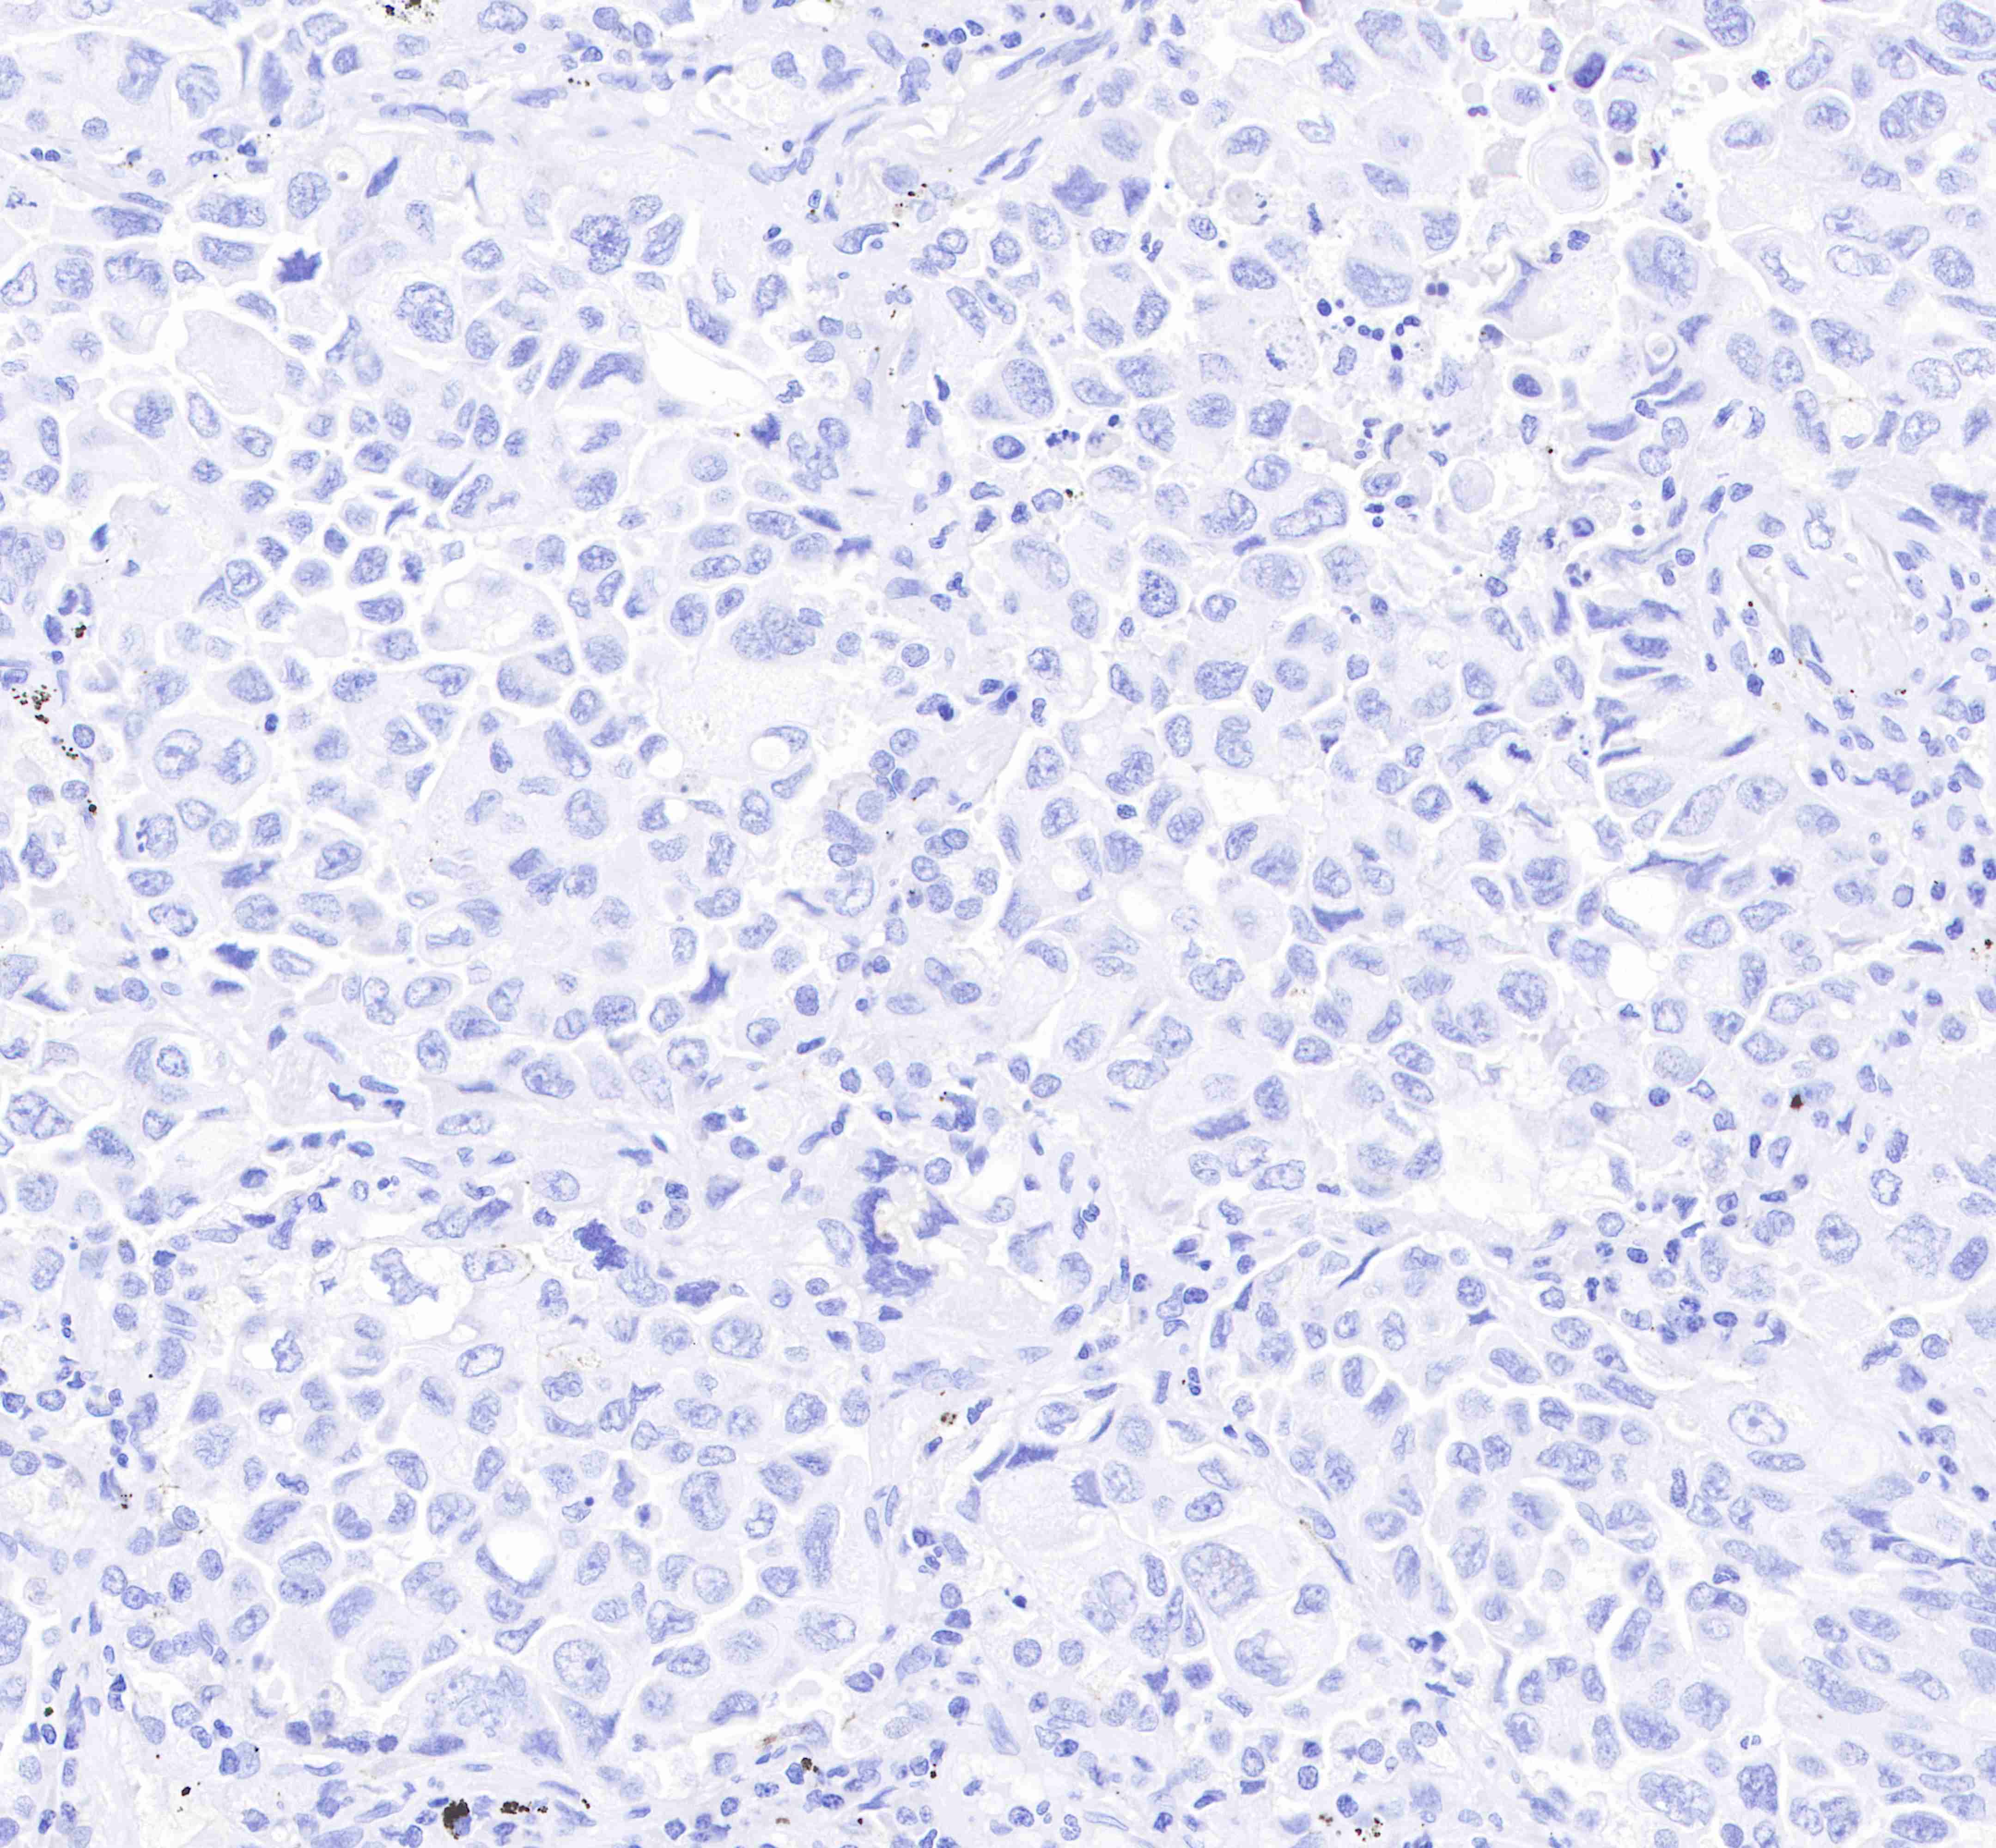

| IHC-P |

1:250 |